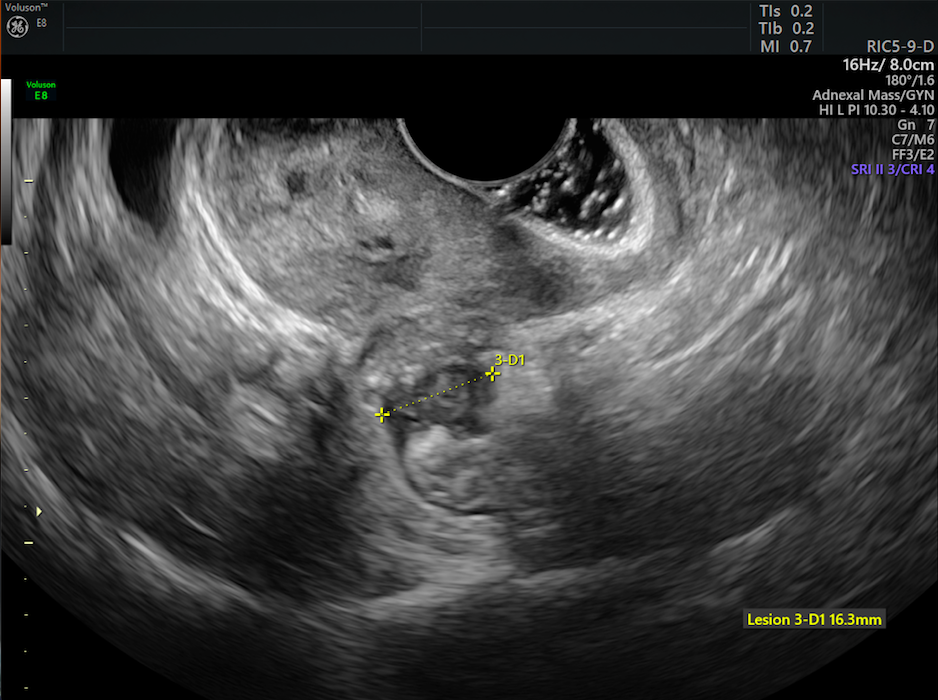

Diagnosing Endometriosis By Comparing Ultrasound Mri Empowered Women S Health